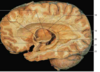

Label the arteries that supply A-C [3]

A

A = anterior cerebral artery (upper

and medial parts of the cortex)

(orange)

B = middle cerebral artery (lateral

areas of the frontal, parietal, and

temporal lobes) (white)

C = posterior cerebral artery (occipital

lobe and inferior parts of the

temporal lobe) (blue)